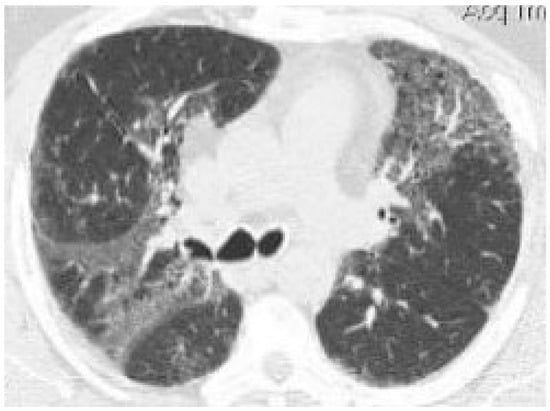

- Phan, T.D.; Lau, K.K.P.; Li, X. Lung bullae an pulmonary fibrosis associated with marijuana smoking. Australas. Radiol. 2005, 49, 411–414. [Google Scholar] [CrossRef] [PubMed]

- Hartman, T.E.; Primack, S.L.; Kang, E.Y.; Swensen, S.J.; Hansell, D.M.; McGuinness, G.; Muller, N.L. Disease progression in usual interstitial pneumonia compared with desquamative interstitial pneumonia: Assessment with serial CT. Chest 1996, 110, 378–382. [Google Scholar] [CrossRef] [PubMed]